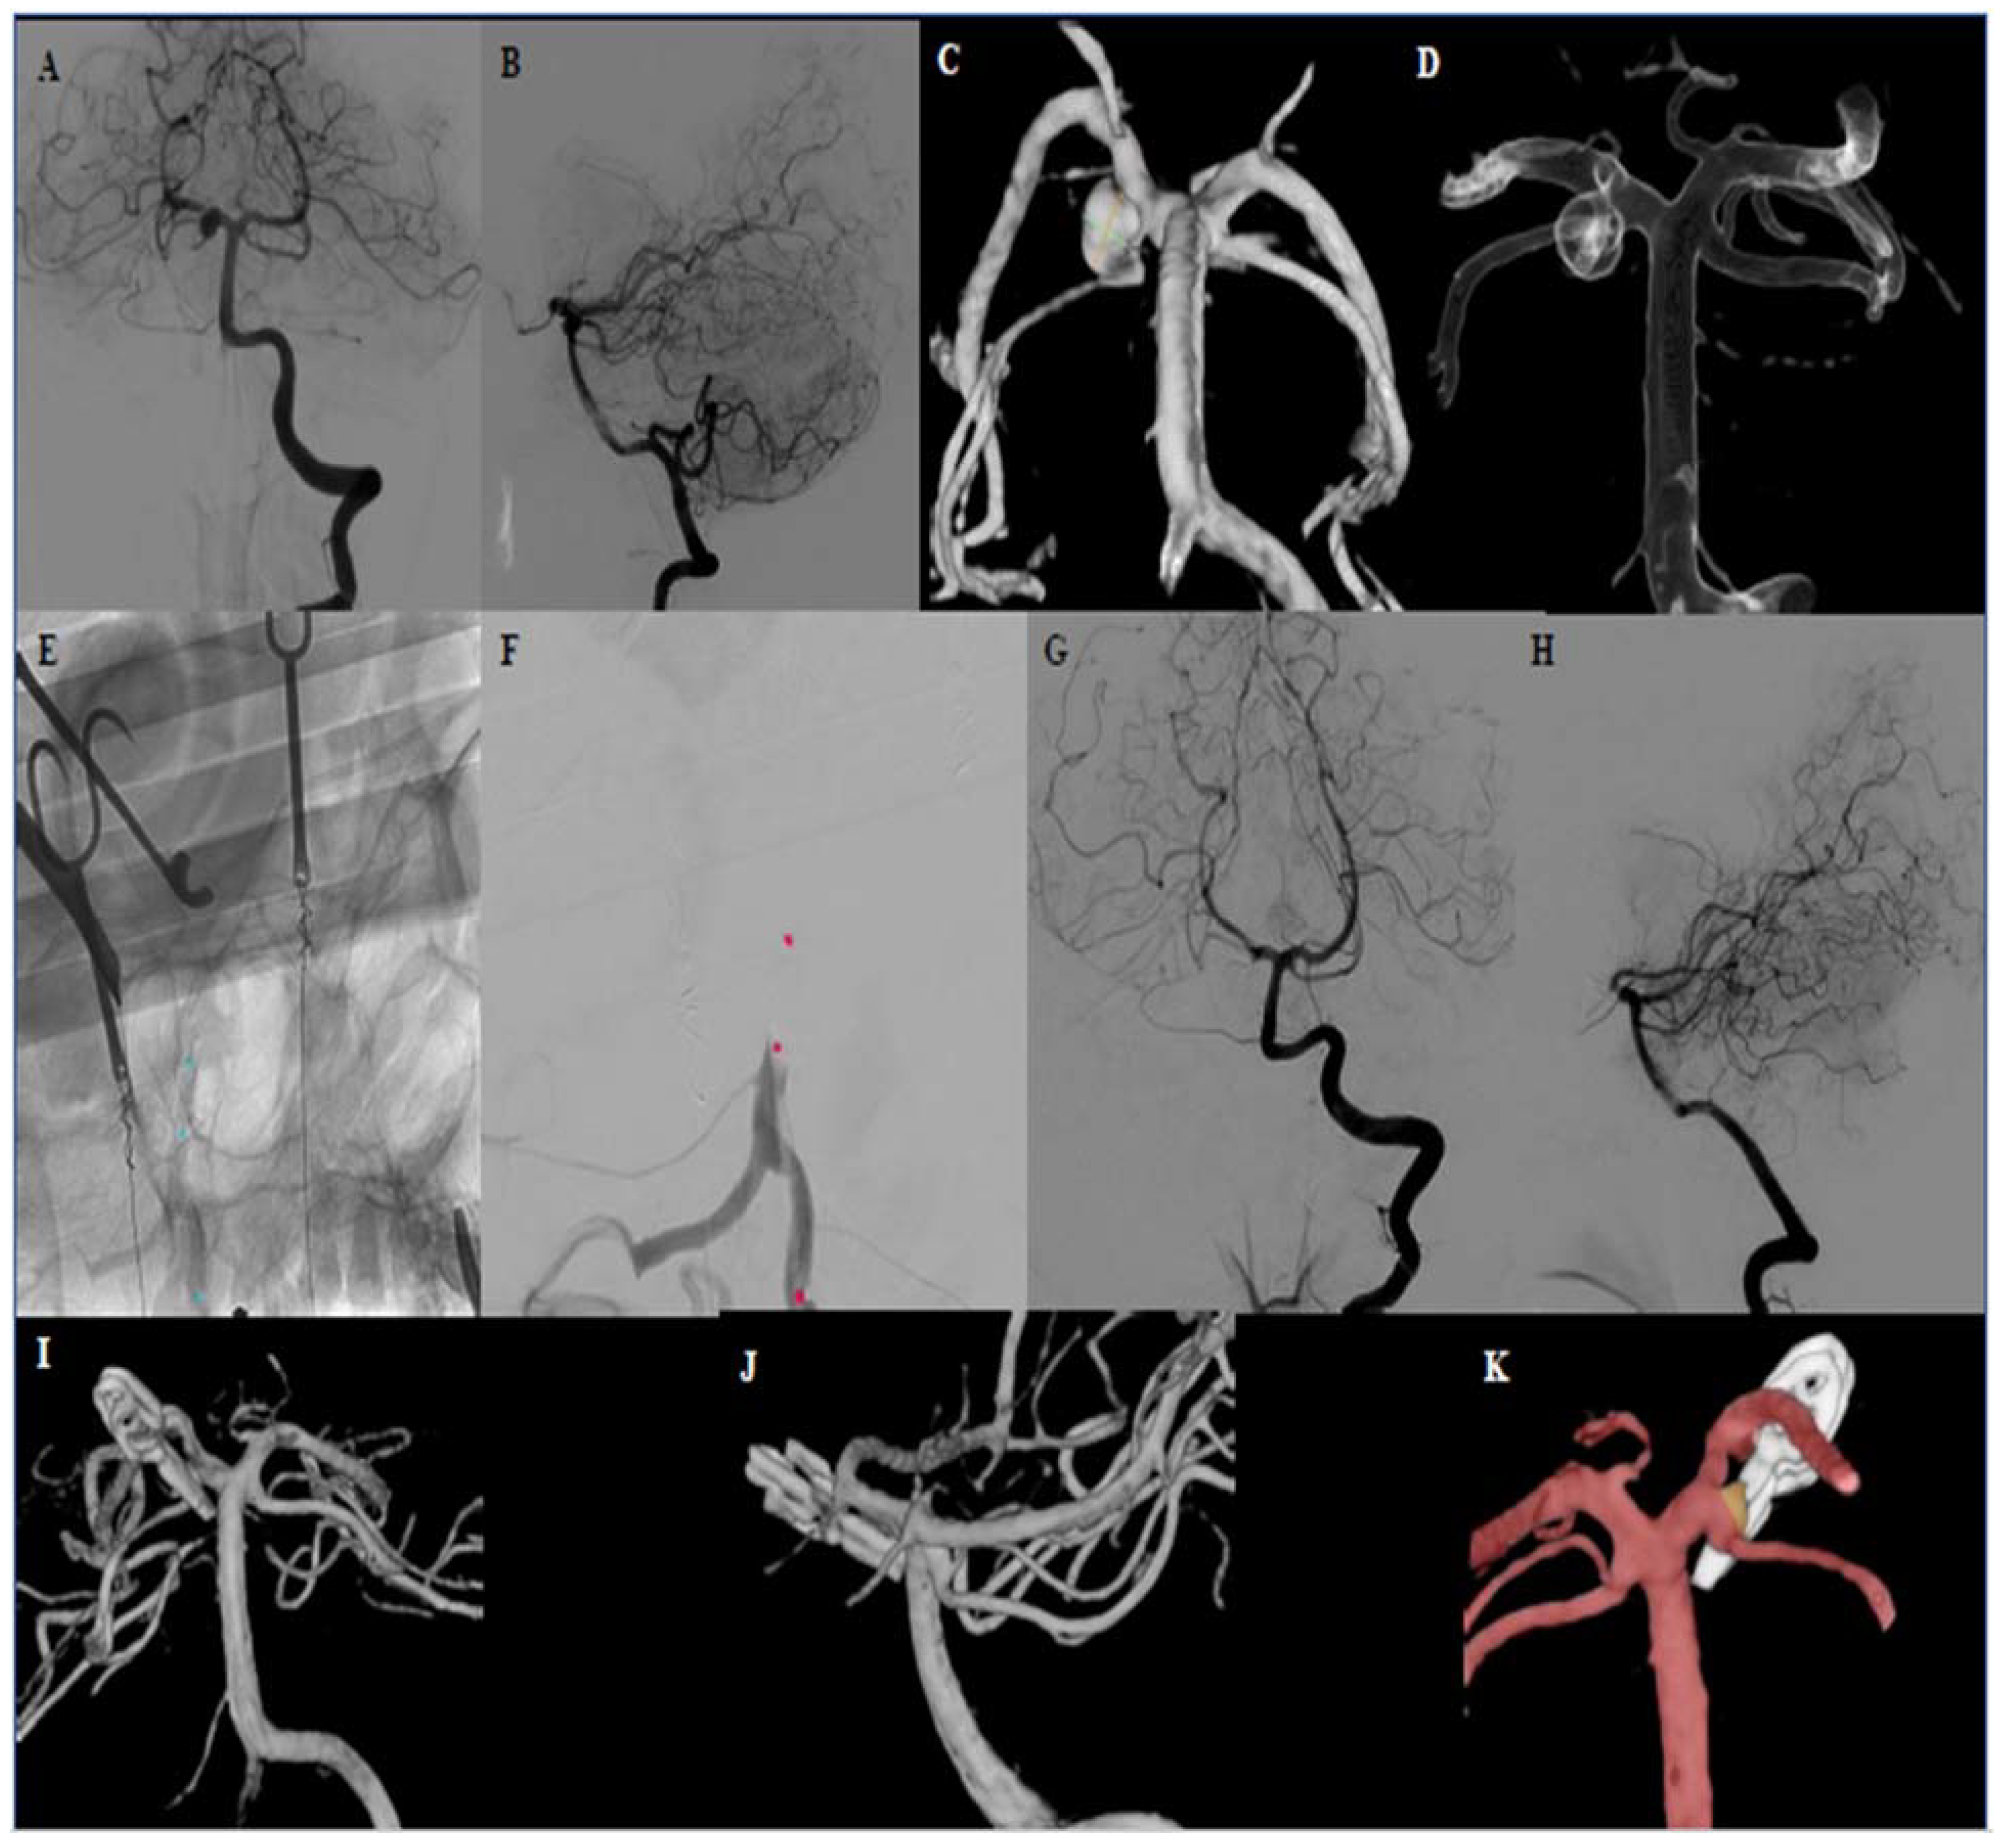

| 1 | 53 | Female | Basilar tip aneurysm Bilateral PCA and SCA are leaving from the aneurysm base | 16 × 16 × 15 | no | Dizziness attack and syncope, SAH | 4 | 5/5 | 3 | 6 | 1 |

| 1 | 9 | 1 | Complete occlusion of the aneurysm All branches open | ASCENT® 4 × 7 balloon (DePuy Synthes) | None |